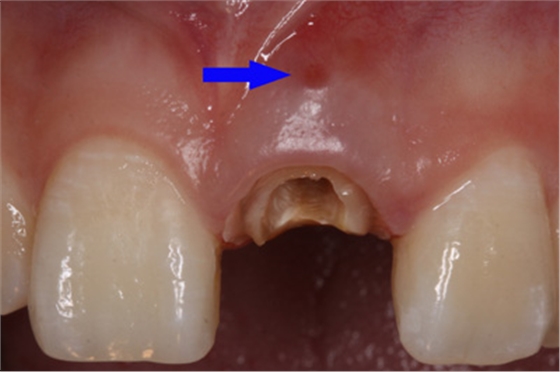

患者外院螺紋樁核加樹脂冠

唇側(cè)出現(xiàn)瘺管